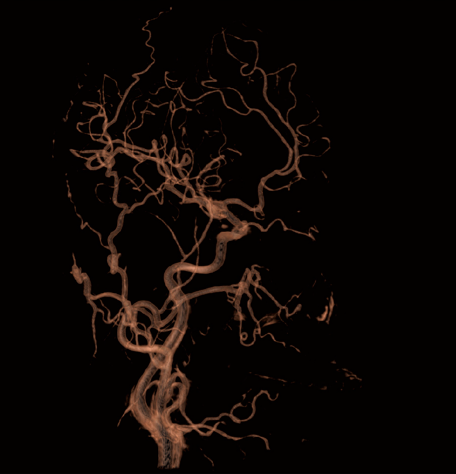

The Power of Tomography in the operating room

Combine live images with 2D and 3D projections along with tomographic slices on site

Clinical Images